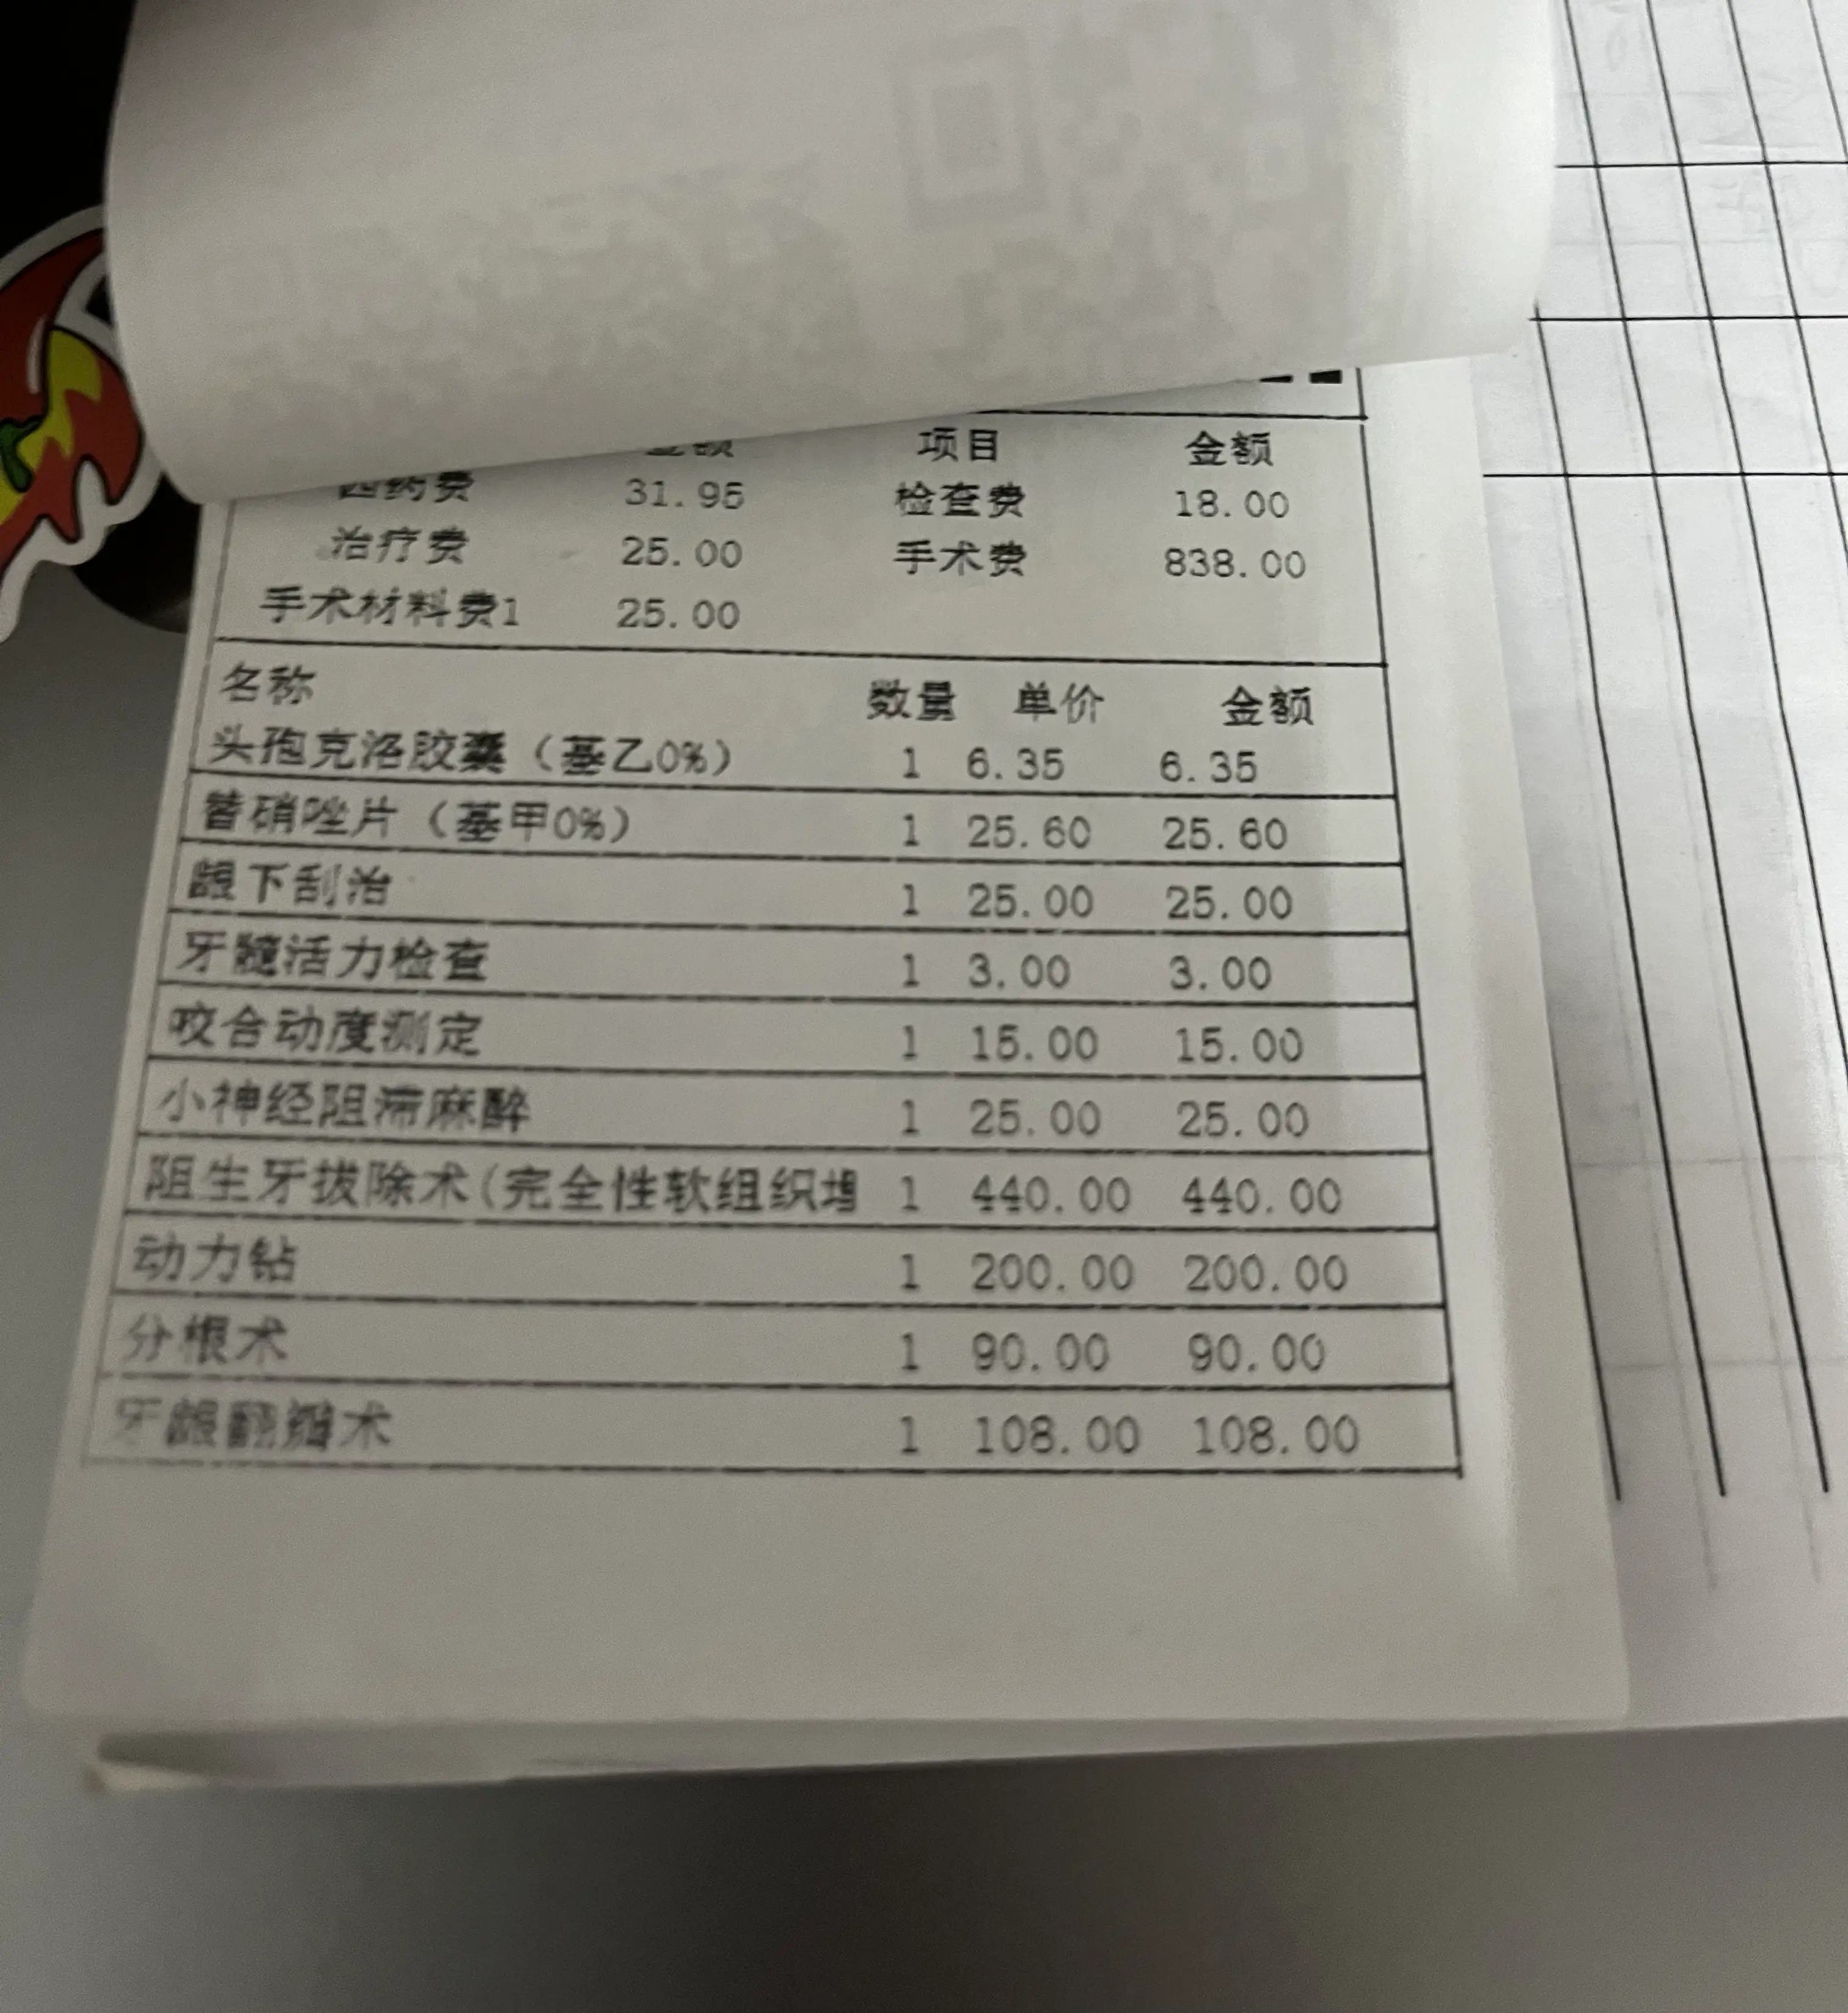

本次门诊终于到达了医保的起付线,账单是900¥多:

微信支付409¥现大洋就搞定了。